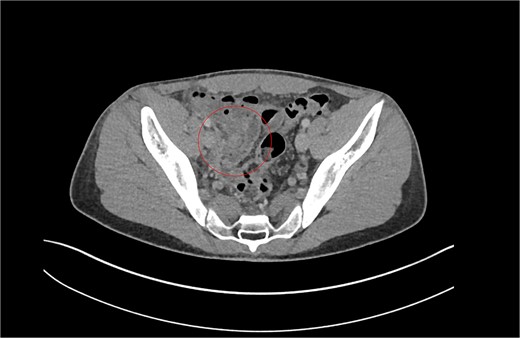

With a differential diagnosis of stump appendicitis versus nephrolithiasis, a CT KUB was done which revealed no significant findings in the appendix or kidneys—the differential was revised to mesenteric adenitis or inflammatory bowel disease. The patient was counseled to be booked for an outpatient colonoscopy. However, in view of ongoing symptoms, serial examinations and investigations revealed a rising white cell count and CRP to 264. The patient was started on intravenous (IV) antibiotics. A formal CT CAP demonstrated mural thickening and enhancement of the caecal pole and fat stranding (Fig. 2). With a diagnosis of stump appendicitis, IV antibiotics were escalated to metronidazole and piperacillin-tazobactam.

Patient B. Appendiceal stump of Patient B identified within the red circle on CT scan before the second operation.